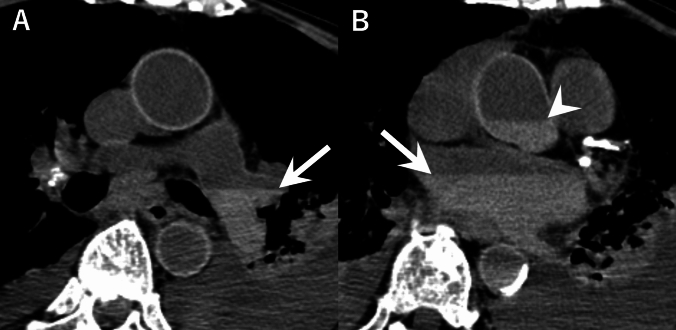

目的:尸体计算机断层扫描(PMCT)通常显示心脏和血管结构中的血凝块和沉淀。我们检查了这些死后发现与院内死亡的死前临床和实验室参数之间的关系。材料和方法:这项前瞻性研究包括114例死后24小时内进行PMCT的非创伤性院内死亡。两名放射科医生评估了左右心房、肺动脉和胸主动脉的高密度区域,并将其分类为血凝块或重力沉降。采用单因素和多因素logistic回归分析死亡前一周的临床和实验室数据。结果:所有解剖部位的观察者间一致性极好(κ = 0.87-0.91)。34-53%的病例在不同部位观察到血凝块或血液沉淀。根据单因素分析,非肺炎感染、阳性血培养和升高的凝血参数(凝血酶原时间-国际标准化比率、活化的部分凝血活酶时间)与重力沉降有关。相反,实体恶性肿瘤和较高的血液学参数(血小板计数、红细胞、血红蛋白、中性粒细胞百分比)与血块形成相关(均p)。结论:死后重力沉降与非肺炎感染有关,而血块形成与较高的血小板计数有关。这些发现为解释PMCT的发现提供了客观标准,并可能有助于评估患者生前的临床状态,特别是在临床信息有限的情况下。

Material and methods: This prospective study included 114 non-traumatic in-hospital deaths where PMCT was performed within 24 h postmortem. Two radiologists evaluated high-density areas in the right and left atria, pulmonary artery, and thoracic aorta, and classified them as blood clots or gravitational sedimentation. The clinical and laboratory data from the week before death were analyzed using univariate and multivariate logistic regression.

Results: Interobserver agreement was excellent for all anatomical sites (κ = 0.87-0.91). Blood clot or blood sedimentation were observed in 34-53% of cases across different locations. Per univariate analysis, non-pneumonic infections, positive blood cultures, and elevated coagulation parameters (prothrombin time-international normalized ratio, activated partial thromboplastin time) were associated with gravitational sedimentation. In contrast, solid malignancies and higher values of hematologic parameters (platelet count, red blood cells, hemoglobin, neutrophil percentage) were associated with blood clot formation (all p < .05). Per multivariate analysis, non-pneumonic infections maintained strong associations with gravitational sedimentation across all sites (p < .05), while higher platelet counts independently predicted blood clot formation in the right atrium, left atrium, and thoracic aorta (p < .05).